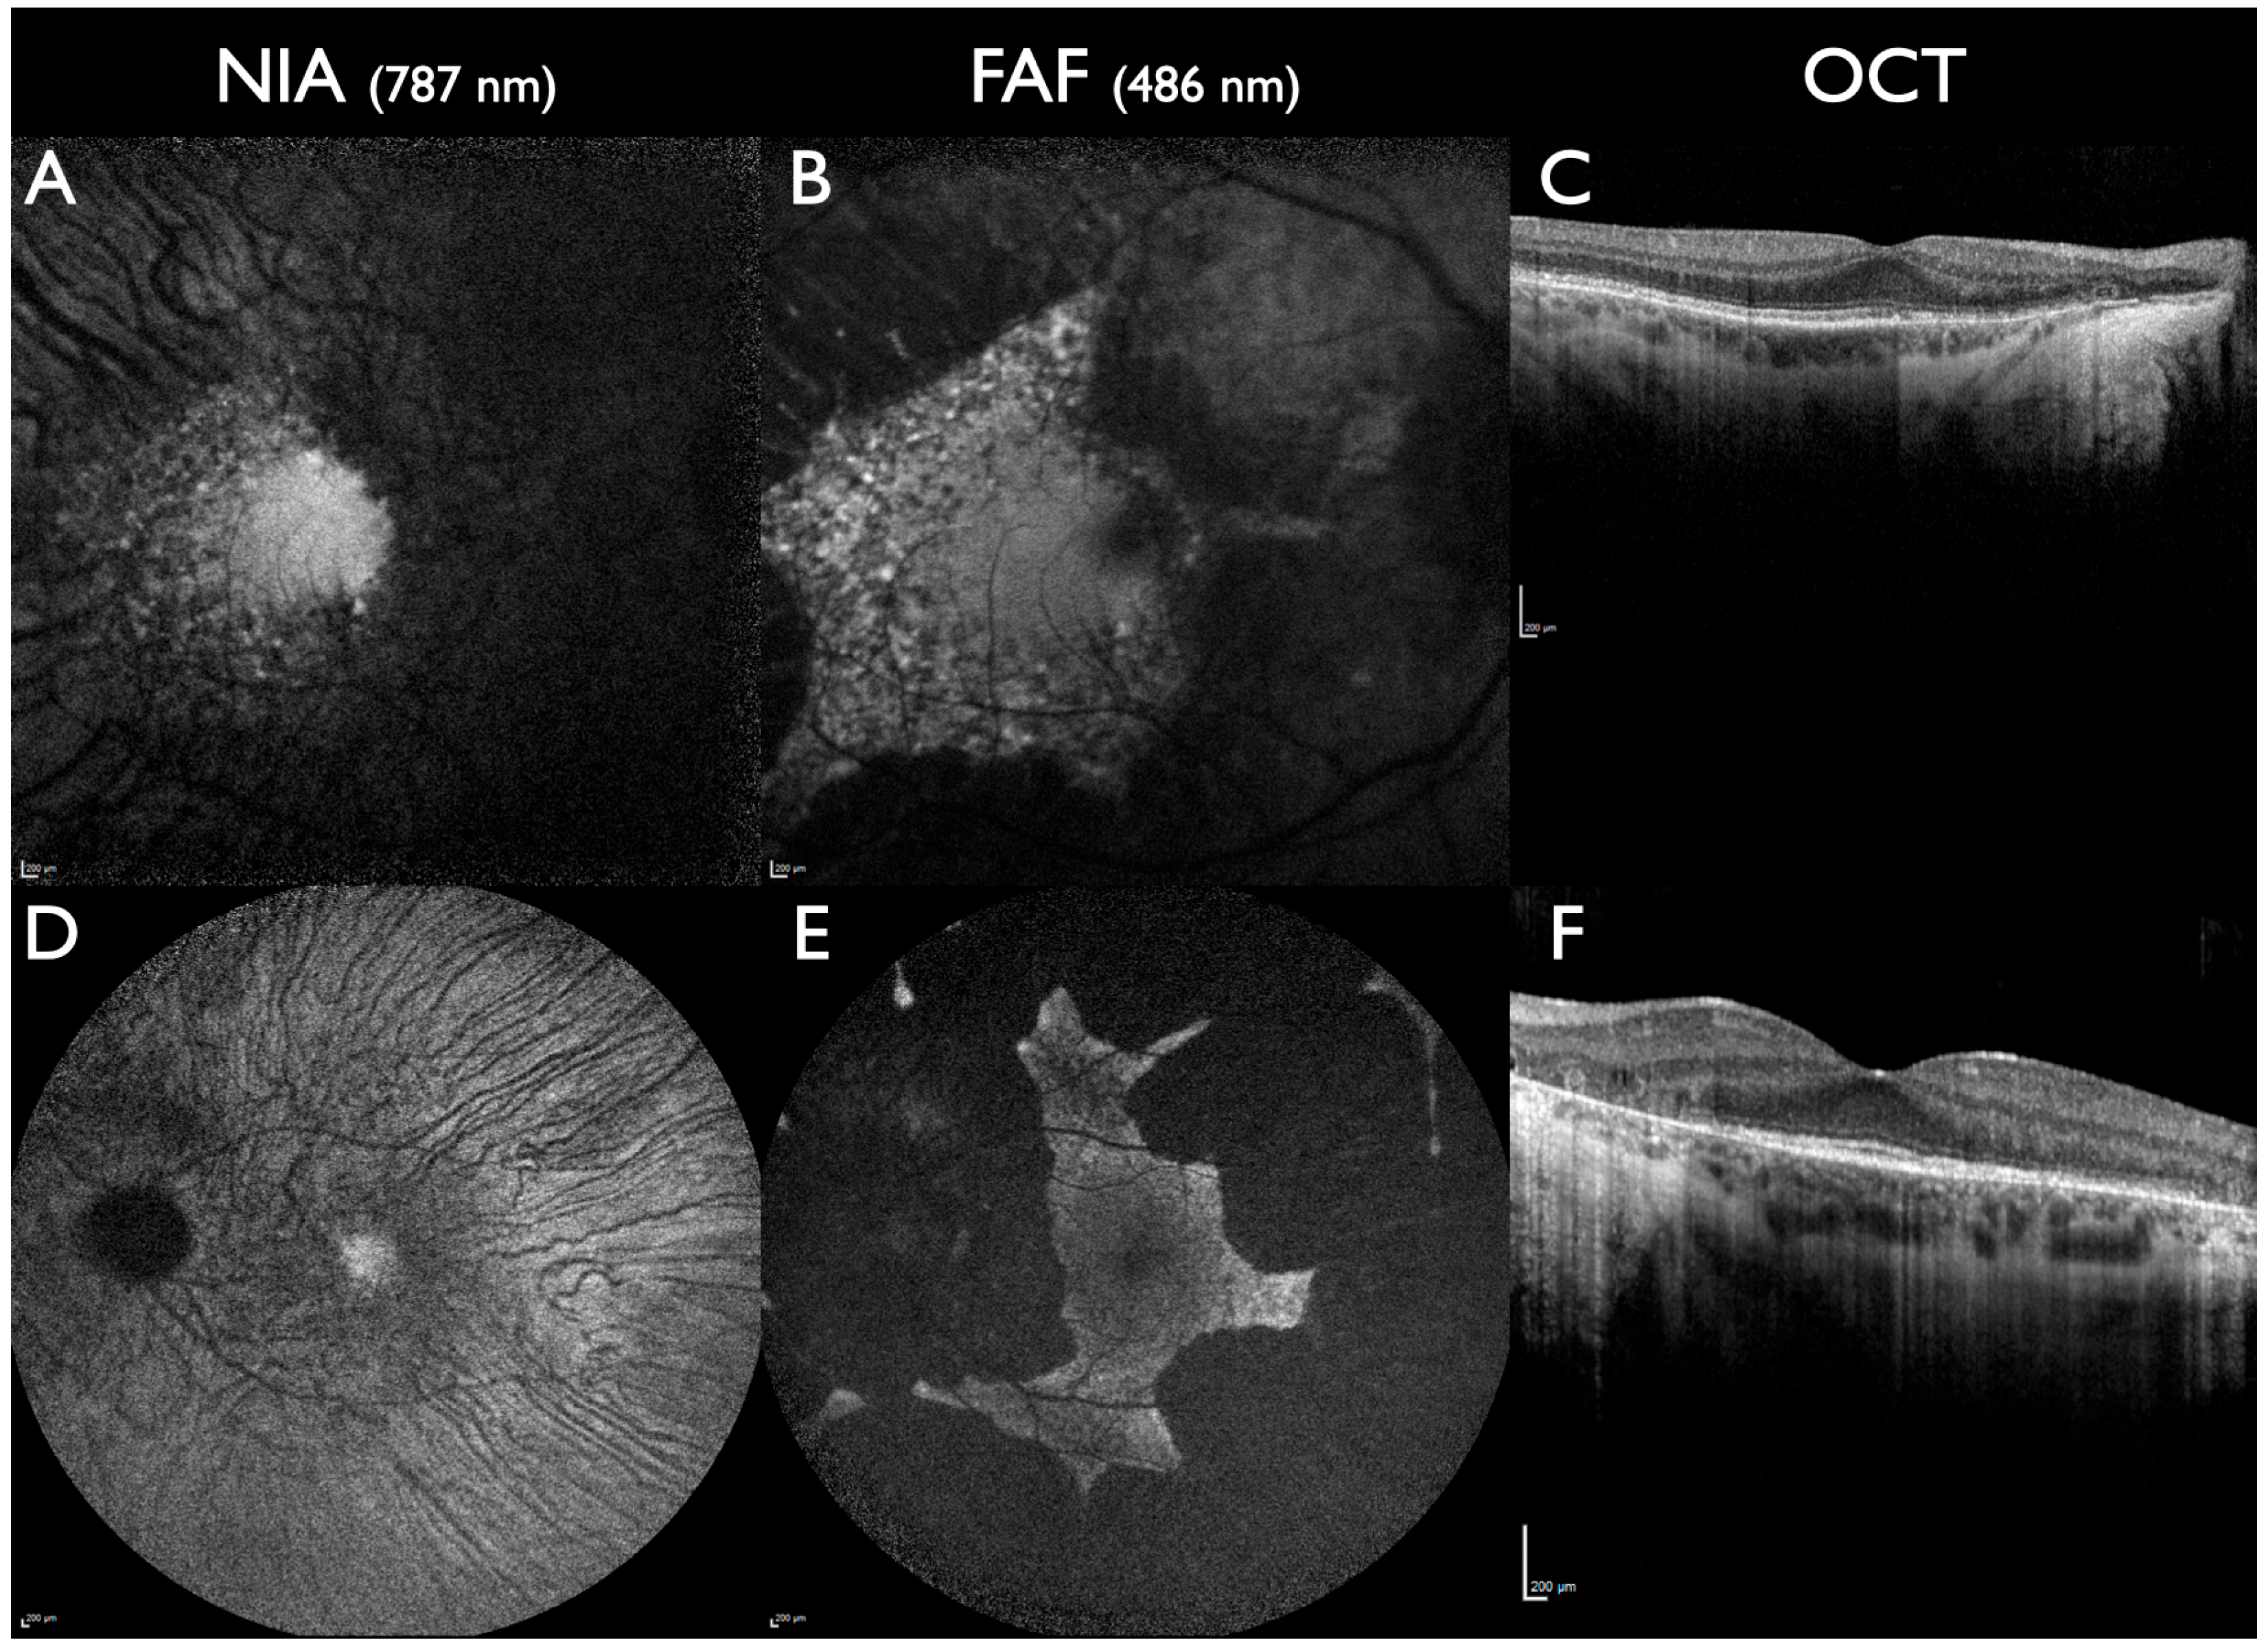

Figure 2. ABCA4-associated IRD. All patients had two pathogenic or likely pathogenic gene sequence variants in the ABCA4 gene. (AC): A 16-year-old male. Visual acuity 20/200 on the right eye, 20/400 on the left eye, and central scotomas. Severe loss of NIA and FAF intensity at the posterior pole with a small area of preserved subfoveal NIA and FAF. Towards the periphery, the ring of increased NIA intensity is slightly peripheral to the ring of increased FAF intensity (yellow arrow). (DF): A 37-year-old male: visual acuity 20/200 on both eyes and central scotomas. Fleck-like areas of abnormal intensity are more extensive in NIA compared to FAF. A parapapillary fleck can be detected with NIA, but not with FAF or fundus photography (yellow arrows). (GI): A 15-year-old patient with CRD. Visual acuity 20/200 on both eyes and central scotomas. Multiple fleck-like lesions in NIA and FAF, more reduced intensity in NIA compared to FAF. The area of preserved peripapillary RPE is smaller in NIA compared to FAF. All scale bars indicate 200 µm.

The rate of disease progression is higher when measured with NIA compared to FAF [43]. During progression, NIA shows a faster reduction in intensity and less flecks with increased intensity compared to FAF. Serial NIA and FAF testing shows that the evolution of flecks with increased FAF intensity is preceded by alterations in NIA intensity in that location [33,44,45,46,47,48]. Consequently, the area of NIA lesions is larger compared to FAF [49,50,51]. In several patients, the area of reduced NIA intensity is larger than the loss of the ellipsoid zone in OCT and, therefore, is the earliest sign of RPE cell loss prior to photoreceptor decline [52,53,54,55]. A reduced subfoveal NIA intensity is usually associated with marked loss of visual acuity [56]. In contrast, in patients presenting a phenotype with preserved foveal structures (foveal sparing) good visual acuity corresponds to normal or near-normal subfoveal NIA intensity [57].

Peripapillary-preserved RPE is another biomarker that is frequently, but not exclusively, seen in ABCA4-associated CRD (Figure 2). This area can be detected with NIA and FAF but is smaller in NIA [58,59]. In severely progressed CRD, FAF can still detect fleck-like areas with relatively increased FAF intensity, whereas NIA intensity is markedly reduced or unmeasurable throughout the RPE.